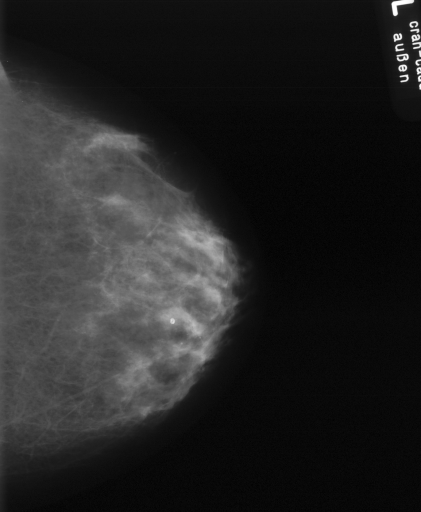

In this series of experiments, we randomly selected three categories from IRMA dataset (namely, breast, foot and lung), and for each category we choose 5 random images from that class (Figures 5, 6 and 7 show these images). When we find “4 out of 180” (4/180) and “8 out of 180” (8/180) projections via micro-DE (tasks that cannot be performed via brute-force), then the question is what can we say about the reconstruction error, in terms of correlation between original and reconstructed images, when we compare evolutionary approximation with the case that we can manage via exhaustive search, namely “4 out of 16” (4/16)? Can micro-DE reach at least the same correlation (similarity) as the brute-force case in lower dimensions? If yes, we may have more confidence in using micro-DE in practice where we cannot apply brute force for benchmarking or direct use, especially for higher dimensions (i.e., the number of projections).

For finding optimal projections based on micro-DE (4 out of 180), we set the parameters of micro-DE to be NFC, , , , and we run each experiment 30 times. For optimal projections based on micro-DE (8 out of 180), we set NFC, , , , and we run each experiment 30 times. The results are presented in Tables 2, 3 and 4. In all cases, micro-DE (MDE) with 4/180 reaches the same correlations as brute force (BF) for 4/16. Of course, MDE finds different projections as it is searching the entire search space of . However, that the same level of reconstruction accuracy can be achieved establishes the reliability of MDE as a practical solution that may even produce a higher-level of uniqueness for Radon barcodes as 4 projections are selected among all 180 angles (the increased uniqueness needs to be verified by applying the Radon barcodes for image retrieval). On the other hand, MDE for 8/180 clearly increases the correlation with statistical significance. This is very encouraging as we can generate more expressive Radon barcodes using a higher number of projections.

| image | BF (4/16) | MDE (4/180) | MDE (8/180) | |||

|---|---|---|---|---|---|---|

| b1 | [22,67,123,157] | 0.83 | [30,50,120,160] | 0.83 | [70,130,30,120,100,150,170,50] | 0.89 |

| b2 | [33,67,123,169] | 0.83 | [30,70,120,160] | 0.83 | [170,140,150,60,40,80,20,110] | 0.89 |

| b3 | [22,67,123,157] | 0.81 | [30,50,120,160] | 0.81 | [150,170,10,70,40,130,110,50] | 0.85 |

| b4 | [11,56,146,169] | 0.81 | [20,60,120,160] | 0.80 | [160,20,120,170,40,30,130,70] | 0.86 |

| b5 | [11,56,112,157] | 0.81 | [20,60,120,160] | 0.81 | [80,20,120,60,160,90,10,140] | 0.86 |